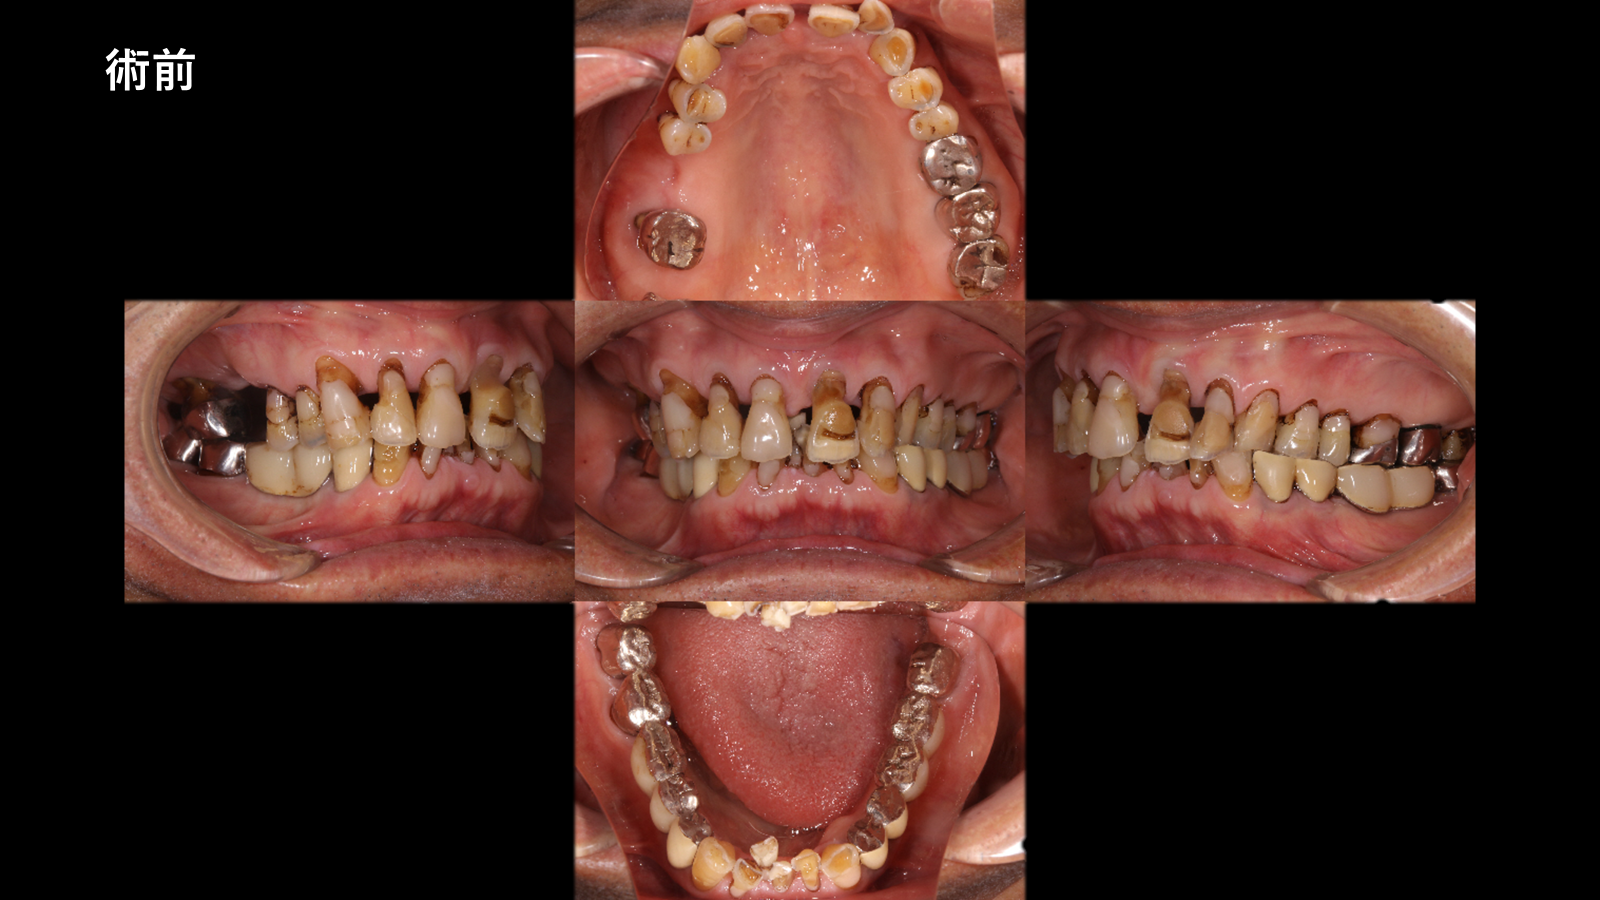

抜歯即時義歯を経て、最終的に精密設計のキャストパーシャルデンチャーへ移行した包括的再建症例です。機能回復と審美性の両立を目指した治療内容をご紹介します。

| 主訴 | 80代男性 虫歯で噛めないので、全体的に見て欲しい。 |

| 所見 | 本症例では、咬合の不安定から歯の破折や重度の虫歯により多数歯の動揺および咬合崩壊が認められました。保存困難歯を抜歯後、即時義歯により咬合支持を確保し、治癒期間を経て最終的に自費キャストパーシャルデンチャーへ移行しました。 最終補綴では、支台歯の設計・クラスプ位置・咬合関係を精密に計画し、機能的安定と審美的改善を両立させました。 |